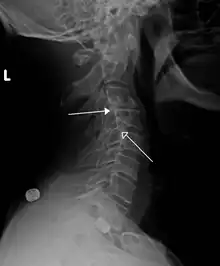

Grade 1 retrolistheses of C3 on C4 and C4 on C5 | |

A retrolisthesis is a posterior displacement of one vertebral body with respect to the subjacent vertebra to a degree less than a luxation (dislocation). Retrolistheses are most easily diagnosed on lateral x-ray views of the spine. Views where care has been taken to expose for a true lateral view without any rotation offer the best diagnostic quality.

Since the vertebral body in a retrolisthesis moves in a posterior direction, the grading used for spondylolistheses is of little use. It is however useful to divide the anterior to posterior dimension of the intervertebral foramina (IVF) (4) into four equal units. A posterior displacement of up to ¼ of the IVF is graded as Grade 1, ¼ to ½ as Grade 2, ½ to ¾ as Grade 3, ¾ to total occlusion of the IVF as Grade 4. Alternatively, a measurement of the amount of displacement can also made by measuring the bone displacement in millimetres.